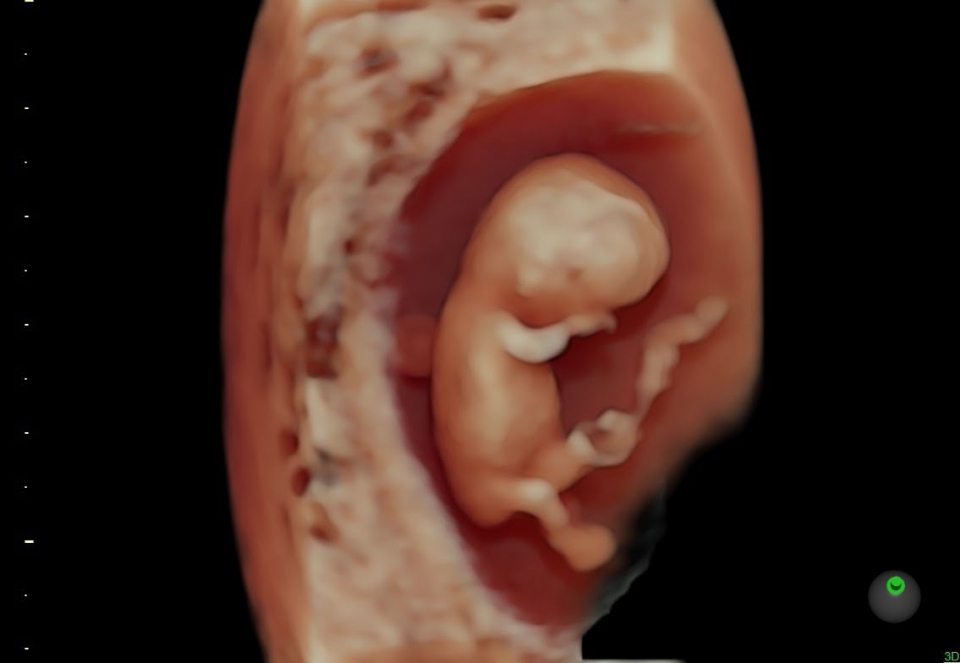

УЗИ аппарат Voluson S10 позволяет проводить обследования высочайшего уровня с максимальной точностью диагностики. Благодаря технологии Voluson Core Architecture достигнут высокий уровень качества изображений с возможностью последующей обработки и анализа даже после проведения скрининга. Технология HDlive делает изображения удивительно реалистичными и объемными.

• HDlive в 3D и 4D - режим перемещаемого виртуального источника освещения - "виртуальная фетоскопия"